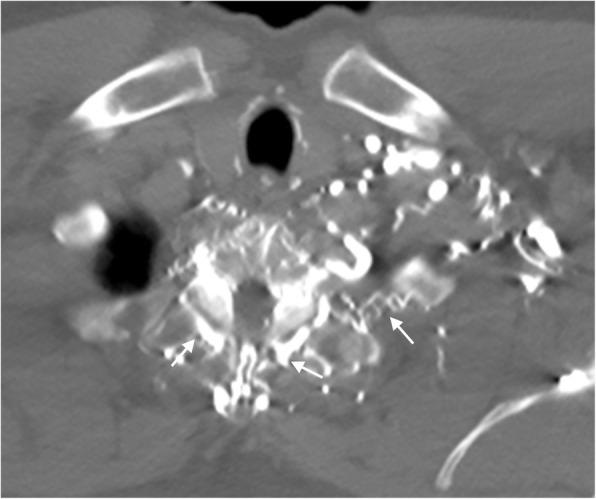

In the healthy patient, blood returns to the heart via classic venous pathways. Obstruction of any one of these pathways will result in blood flow finding new collateral pathways to return to the heart. Although significant anatomic variation exists and multiple collateral vessels are often present in the same patient, it is a general rule that the collateral pathways formed are a function of the site of venous blockage. Therefore, knowledge of typical collateral vessel systems can provide insight in localizing venous obstruction and characterizing its severity and chronicity. In addition, knowledge of collateral anatomy can be essential in interventional procedural and/or surgical planning, especially when placing catheters in patients with venous blockage. In this pictorial review, we provide a systematic approach to understanding collateral pathways in patients with venous obstruction in the upper body.

在健康患者中,血液通过经典静脉途径回流至心脏。这些途径中任何一条受阻都会导致血流寻找新的侧支途径回流至心脏。尽管存在显著的解剖变异,且同一患者体内常存在多条侧支血管,但一般规律是,形成的侧支途径取决于静脉阻塞的部位。因此,了解典型的侧支血管系统有助于定位静脉阻塞并判断其严重程度和慢性化情况。此外,了解侧支解剖结构对于介入操作和/或手术规划至关重要,尤其是在为静脉阻塞患者放置导管时。在本图文综述中,我们提供了一种系统方法,用于理解上身静脉阻塞患者的侧支途径。